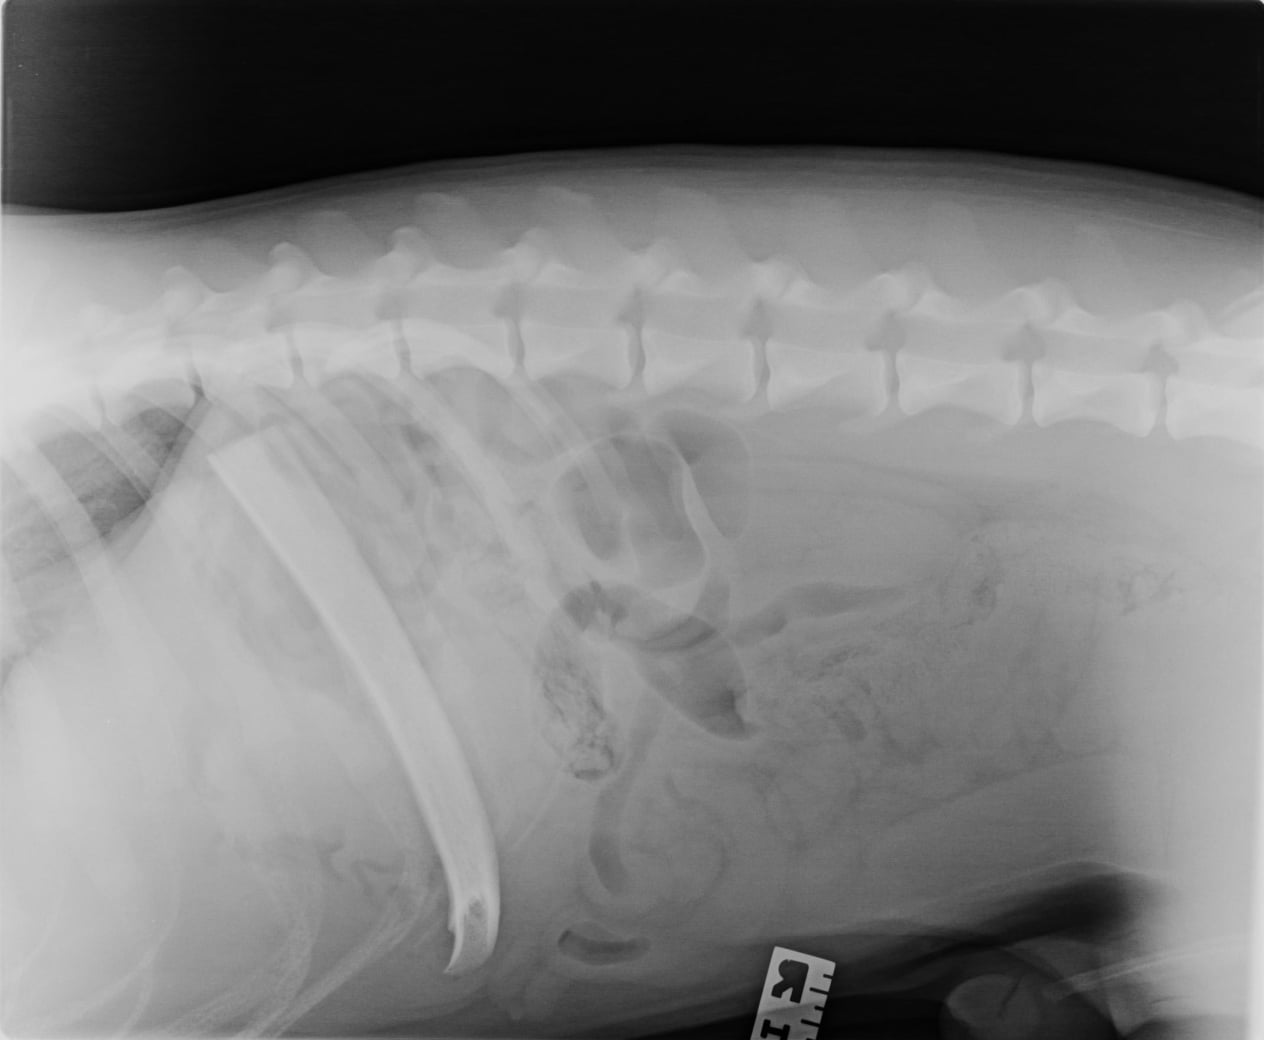

X-rays or ultrasound to find the location of the bone